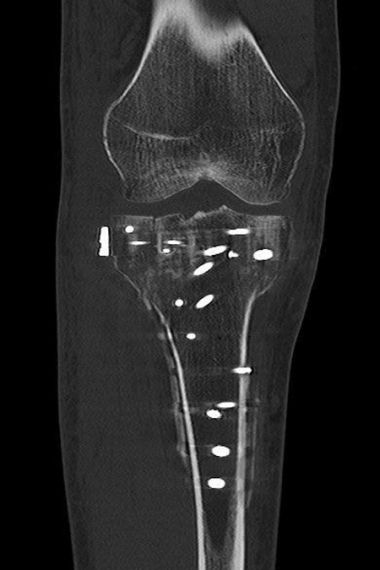

Bild Patient zeigt nach der OP seine Narbe

„Ich bin hinter meinen Kindern her gelaufen, dabei ist mir ganz blöd das rechte Knie weggeknickt. Dass man sich dabei so verletzten kann, finde ich immer noch erstaunlich. Nach der Operation musste ich zunächst mit Unterarmstützen eine Zeit lang entlasten und habe viel an der Bewegung gearbeitet. Heute kann wieder ganz normal gehen. Das Joggen und Rennen muss ich mir noch erarbeiten.“

Im Januar 2023 hier operativ versorgte bikondyläre Tibiakopffraktur eines 38 jährigen Familienvaters. Insbesondere die außenseitige hinten liegende Bruchsituation erfordert eine dorsale Plattenlage über einen erweiterten posterolateralen Zugang und intraoperative arthroskopische Kontrolle. Es konnte eine stufenfreie Rekonstruktion und ein nachfolgend sehr schönes funktionelles Ergebnis erzielt werden.